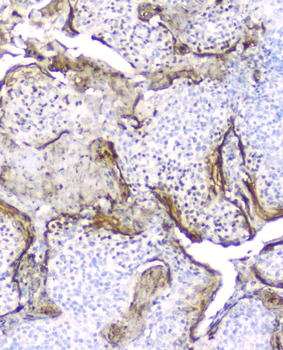

IHC analysis of Elafin using anti-Elafin antibody. Elafin was detected in paraffin-embedded section of human tonsil tissue. Heat mediated antigen retrieval was performed in citrate buffer (pH6, epitope retrieval solution) for 20 mins. The tissue section was blocked with 10% goat serum. The tissue section was then incubated with 2 µg/ml mouse anti-Elafin Antibody overnight at 4°C. Biotinylated goat anti-mouse IgG was used as secondary antibody and incubated for 30 minutes at 37°C. The tissue section was developed using Strepavidin-Biotin-Complex (SABC) with DAB as the chromogen.